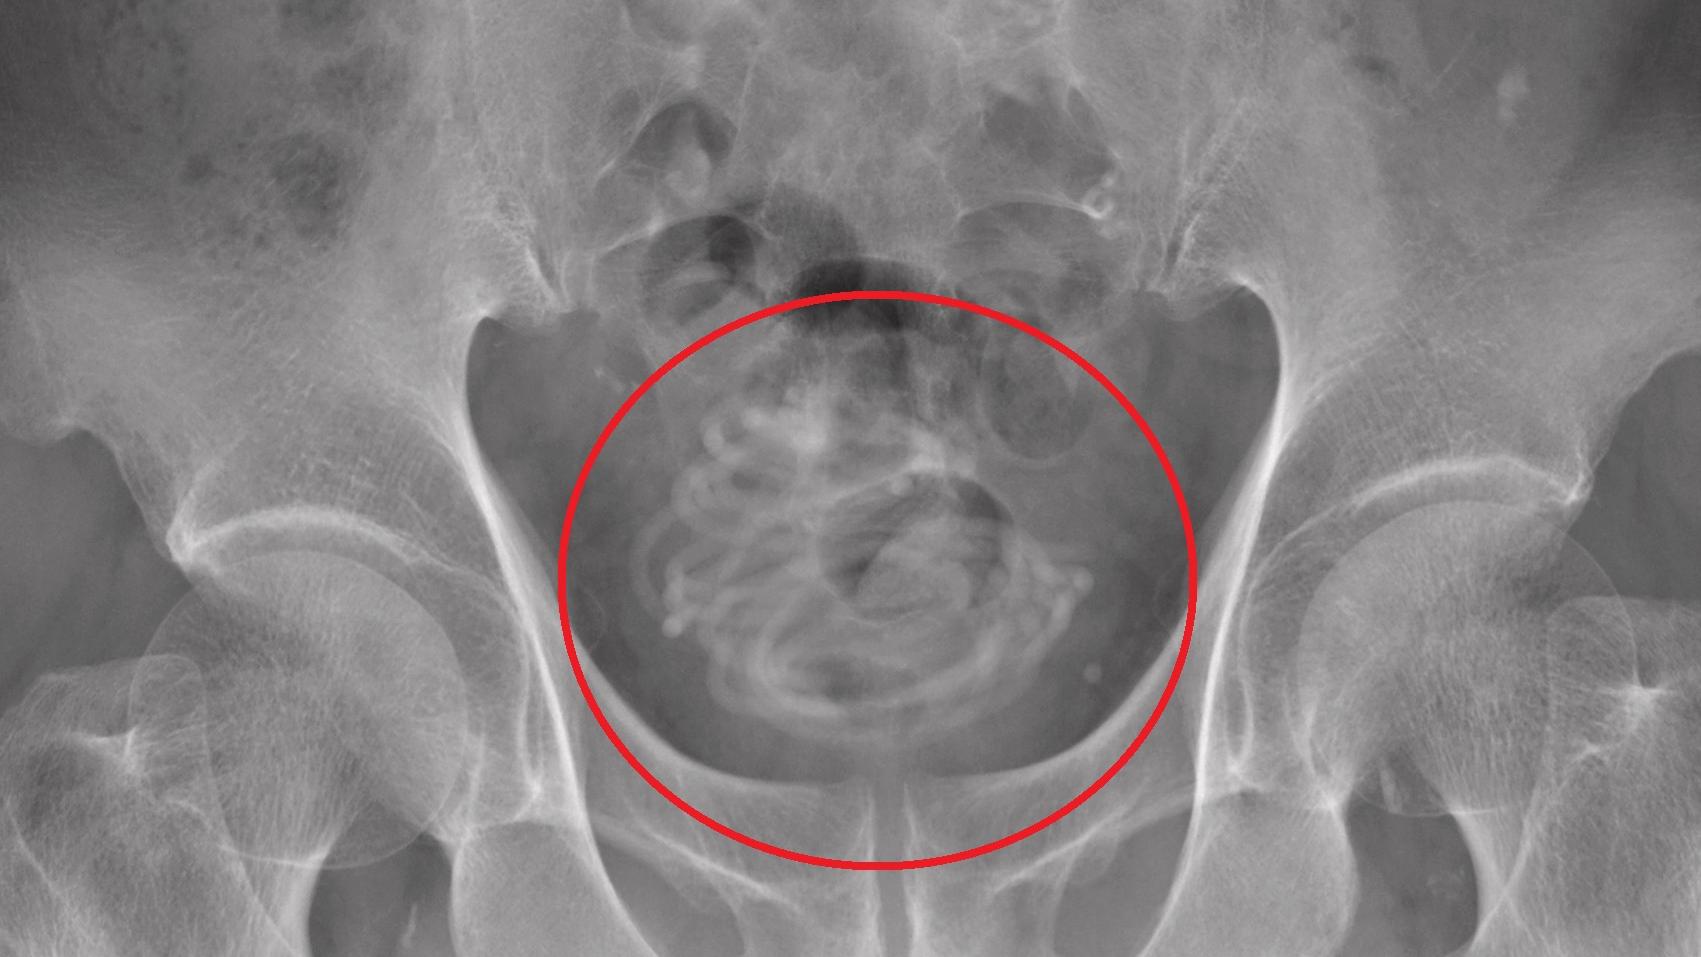

• 膠製跳繩在老翁膀胱裡纏成一團。(互聯網)

日本七旬翁將2.3米長跳繩塞進尿道 醫生嚇呆:點樣做到?